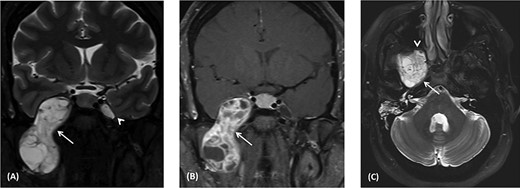

(A) Image-guided tumor removal from petrous carotid artery. (B) Image-guided intraoperative picture status post-complete tumor removal from trigeminal and middle cranial fossa.

The patient underwent an image-guided endonasal endoscopic tumor removal starting by endoscopic medial and posterior walls maxillectomies to control the tumor removal from the lateral sphenoid sinus and the infratemporal fossa after cauterization of the maxillary artery and sphenopalatine artery branches feeding the tumor. The tumor was dissected and removed from the cavernous (Fig. 3A) and petrous carotid artery in the middle cranial fossa (Fig. 3B). The middle cranial fossa’s dura was intact during the tumor removal (Fig. 3C). All the steps of tumor removal were controlled and monitored under image-guided navigation for accurate localization of tumor removal and avoidance of violation to the middle cranial fossa’s dura, or the brain, and the internal carotid artery in its cavernous and petrous segments (Fig. 4a and b).